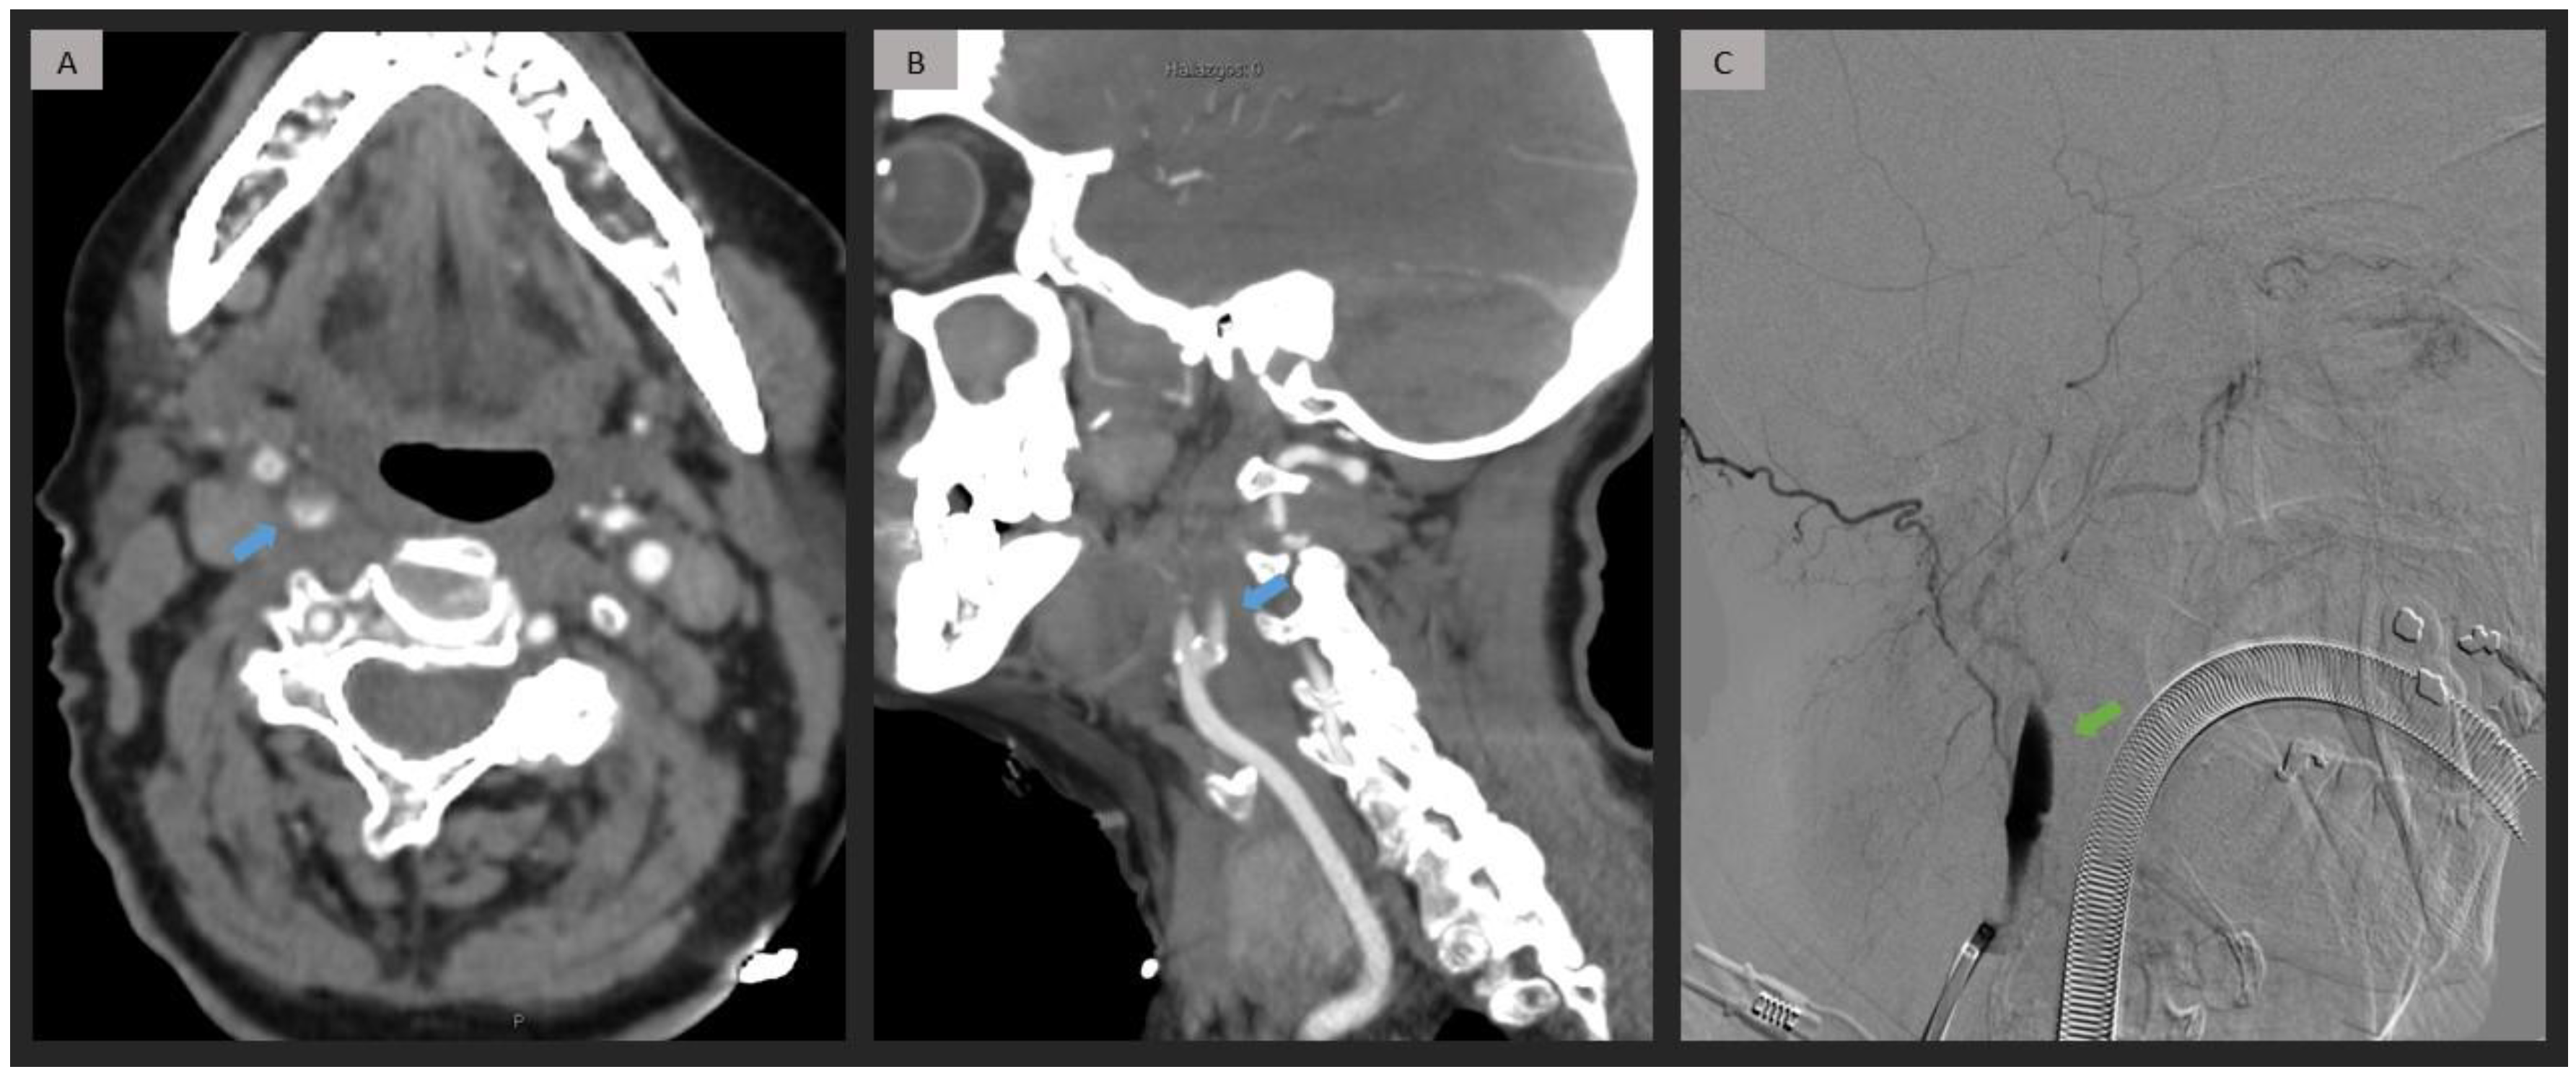

2.4. CTA Analysis

2.5. DSA Analysis

3. Results

4. Discussion